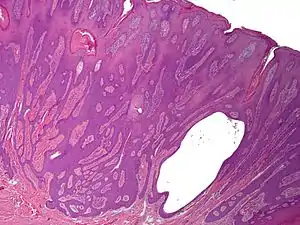

Syringofibroadenoma

Syringofibroadenoma is a cutaneous condition characterized by a hyperkeratotic nodule or plaque involving the extremities.[1]: 668